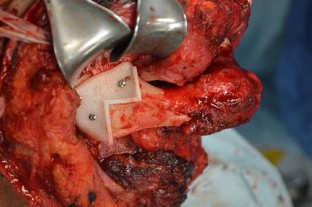

At present, mandibular reconstruction with a fibular free flap is the gold standard for functional and esthetic rehabilitation after oncological surgery. The purpose of this study was to describe the computer-assisted mandibular reconstruction procedure adopting the customized solution Synthes ProPlan CMF. The study reports five consecutive patients with benign or malignant disease requiring mandibular reconstruction using a microvascular fibular free flap, pre-operative virtual planning, construction of cutting guides and customized laser pre-bent titanium plates. The surgical technique is discussed in a step-by-step fashion. The average post-operative hospital stay was 18 ± 3 days. Ischemia time was recorded in all five cases, with an average of 75 ± 8 min. No problems were encountered in any surgical step and there were no major complications. Excellent precision of cutting guides and a good fit of pre-bent plates were found on both the mandible and fibula. There was excellent precision in bone to bone contact and position between mandible and fibula graft. Measurement data from the pre-operative and post-operative CT scans were compared. The average difference (Δ) between programed segment lengths and CT control segment lengths was 0.098 ± 0.077 cm. Microsurgical mandibular reconstruction using a virtual surgical planning yields significantly shorter ischemia times and allows more precise osteotomies. The technology is becoming increasingly recognized for its ability to optimize surgical outcomes and minimize operating time. Considering that the extent of resection can be wider than predicted, this results in safer modeling of the fibula only after frozen sections have demonstrated the radicality of resection.